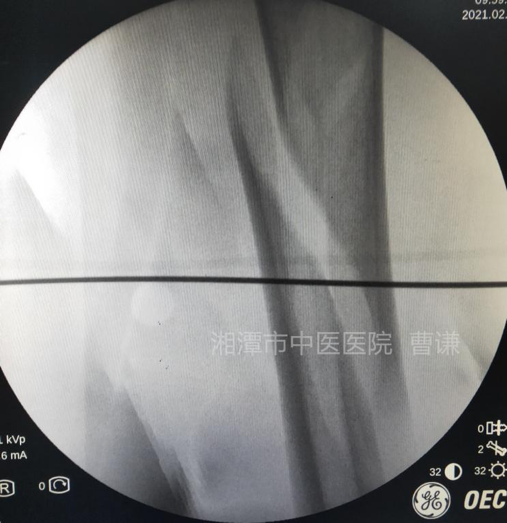

麻醉生效后,常规消毒铺无菌巾,先在体表放置一根克氏针透视,确定骨折端适宜钢丝捆扎的部位。

在透视确定的平面上,分别在大腿前方及稍偏后的外侧做约1.5cm小切口,用一把中号弯钳夹持丝线

透视见钢丝逐渐拧紧并使骨折端靠近复位。